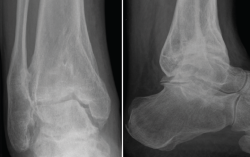

La artrodesis de tobillo sigue siendo, en la actualidad, el procedimiento quirúrgico más común para el manejo de la OA de tobillo. Como todos los procedimientos quirúrgicos, el objetivo es obtener un pie estable, plantígrado y libre de dolor. La alineación óptima para lograr estos objetivos es una flexión plantar/dorsal de 0°, valgo de 5° del retropié, 10° de rotación externa y un desplazamiento posterior del astrágalo respecto al borde anterior de la tibia de 0-10 mm(22,23). La fusión del tobillo tiene como consecuencia un incremento del gasto energético del 3% y puede alcanzar una marcha con el 90% de eficiencia durante la marcha normal(24).

En casos de deformidad severa en varo, esta debe ser reconocida y corregida de manera preoperatoria, ya que la persistencia de la alineación en varo es un factor de riesgo para la pseudoartrosis de la fusión(25). El varo provoca un bloqueo de la articulación mediotarsiana durante la etapa de despegue de la marcha, por lo que se genera una sobrecarga compensatoria en la región lateral del antepié(26). Distintos abordajes se han descrito para la fusión de tobillo: abordaje anterior, lateral transperoneo, miniartrotomía medial y lateral, artroscópico o abordaje posterior, siendo los más comunes los dos primeros. El mejor abordaje debe tener en cuenta el “ápex” de la deformidad y el estado de los tejidos blandos, así como la necesidad de extender o realizar otros abordajes para procedimientos adicionales, siempre manteniendo un puente cutáneo para reducir el riesgo de necrosis.

La fusión o artrodesis de tobillo está indicada solamente si la terapia conservadora no logra mejorar el dolor y/o la rigidez articular. Los resultados de la fusión de tobillo en la articulación con deformidad en varo son poco consistentes. En la mayoría de los casos, se reportan resultados buenos y excelentes tras la fusión con fijación rígida con una adecuada indicación y tomando en cuenta las deformidades asociadas. Saltzman et al. realizaron una revisión de las fusiones no complicadas realizadas durante 11 años (215 artrodesis abiertas en 209 pacientes) y publicaron una tasa de fusión del 91%. Los mismos autores encontraron que era 2 veces más probable que ocurriera una pseudoartrosis si había una deformidad en varo preoperatoria(37). Sam y Wood publicaron una serie de 25 tobillos en 23 pacientes con una artrosis severa con deformidad en varo o valgo > 20°; a todos los pacientes se les practicó una fusión de tobillo a través de un abordaje anterior. El valor preoperatorio promedio de la escala funcional de la AOFAS fue de 25 (11-39), con una progresión postoperatoria a un valor de 43,5 (31-58). La tasa de consolidación fue del 95% y se logró una corrección de la deformidad hasta 5° de alineación neutral(38). La artrodesis artroscópica puede ser utilizada para corregir deformidades severas en el plano coronal. Winston et al.(39) realizaron artrodesis artroscópica en una serie de 105 tobillos con una alteración preoperatoria de la alineación en el plano coronal (> 20°); los autores reportan resultados buenos o excelentes en 83 de los pacientes con una tasa de consolidación del 92,4%.